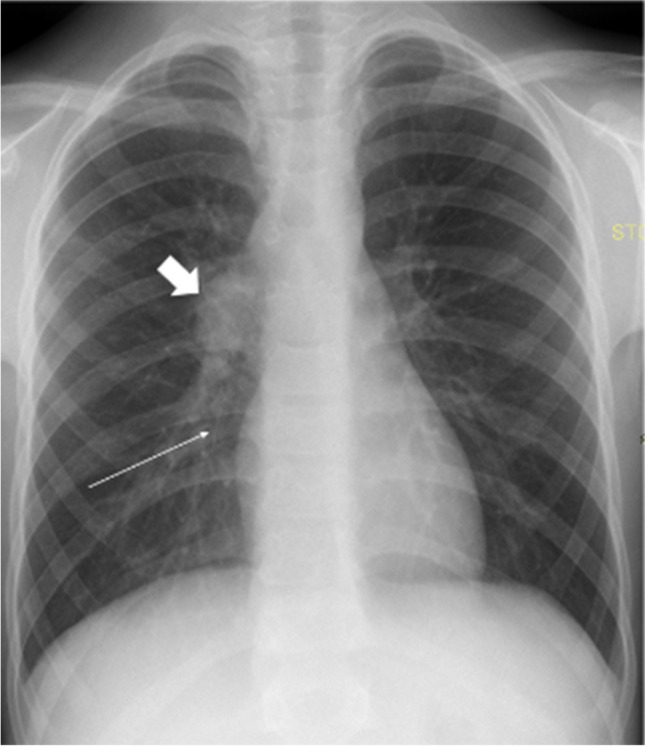

The clinical presentation and blood laboratory analysis of COVID-19 pneumonia is relatively nonspecific. Cough, fever, myalgia, and fatigue are the most common presenting clinical features. On imaging (Figs. 1 and 2), COVID-19 pneumonia in pediatric patients appears as unilateral or bilateral peripheral (subpleural) and/or posterior, and lower lobe-predominant hazy opacities with or without consolidation [19–22]. These findings can be detected on chest radiography; however, chest CT is more sensitive for detection and localization of the imaging findings of COVID-19 pneumonia, especially subtle ground-glass opacities which can only be detected on CT [23–26]. In addition, the CT halo sign is also considered a typical finding of the early phase of pediatric COVID-19 pneumonia [20]. However, the additional CT findings do not affect management in patients with mild to moderate symptoms; therefore, CT is not indicated in these patients and is only typically utilized in patients with a severe COVID-19 pneumonia [25]. Atypical imaging findings, including centrilobular nodules (including tree-in-bud nodularity), cavitation, pleural effusion, and/or lymphadenopathy, are uncommon findings in pediatric COVID-19 pneumonia. Consequently, when present, these atypical imaging features should raise strong consideration for alternative diagnoses [20].

Fig. 1.

Images in a 17-year-old girl with coronavirus disease 2019 (COVID-19) who presented with fever, cough, and fatigue. a Anteroposterior supine chest radiograph shows bilateral peripheral opacities predominately in the basal segments of the lungs. b Axial non-contrast-enhanced lung window computed tomography image shows the typical signs of COVID-19 in children: subpleural and peripheral consolidations in basal and posterior lung segments surrounded by ground-glass opacities (the halo sign)

Fig. 2.

Coronal (a) and sagittal (b) contrast-enhanced lung window computed tomography images in a 7-year-old girl with coronavirus disease 2019 show small ground-glass opacities (arrows) in the basal and posterior lung segments – these findings were not visible on radiography